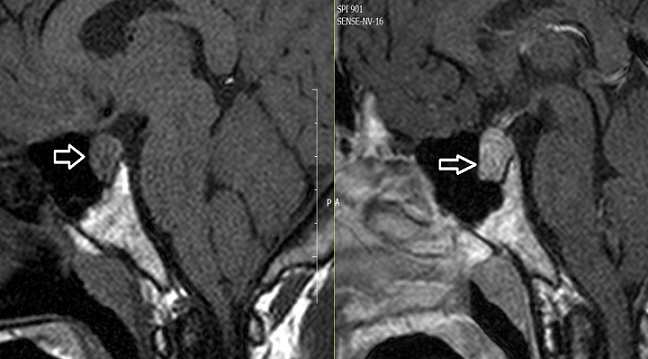

31 years old male patient admitted to the emergency department because of recurrent severe head aches which continued for two years. The patient has been consulted our clinic of internal medicine because of thyroid function abnormalities. Laboratory investigations revealed elevated serum TSH of 8,6 mU/L (normal range (N); 0.34-5,6), free T4 (fT4) of 1,73 (N;0,61-1,12ng/dl), and free T3(fT3) of 5,48 (N; 2,5-3,9pg/mL). Other laboratory parameters were normal. Physical examination revealed stage 3 goiter. The other system examinations were normal. We have learned that two years ago brain computed tomography scan was performed due to head a cheand result was reported as normal. Considering secondary hyper thyroidism pituitary MR was performed. Pituitary MR revealed a 13x18 mm macro adenoma (Figure). The patient under went transphenoidal surgery. Final diagnosis wasTSH secreting adenoma after pathological examination. After surgery head a cheand hyperthyroidism were recovered.